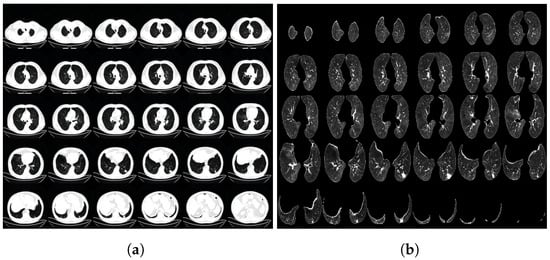

To increase the diversity of the samples, the 3D CT images underwent random rotations with angles within ±15 around the Z-axis of the CT images. Afterward, disease-related regions that might not be easily noticed by the network were cropped, and the cropped images were resized to pixels. For the experimental setup, the dataset was divided into a training set, validation set, and test set in a ratio of 3:1:1. This division ensured that the data were adequately represented for training, model validation, and final evaluation. To provide visual examples, Figure 1 illustrates the CT image data before and after the preprocessing steps, showcasing the impact of the normalization and cropping procedures. Figure 2 illustrates the CT image data before and after the preprocessing steps at a much larger scale.

Figure 2.

The CT image data before and after preprocessing (larger scale), (a) is before preprocessing and (b) is after preprocessing.